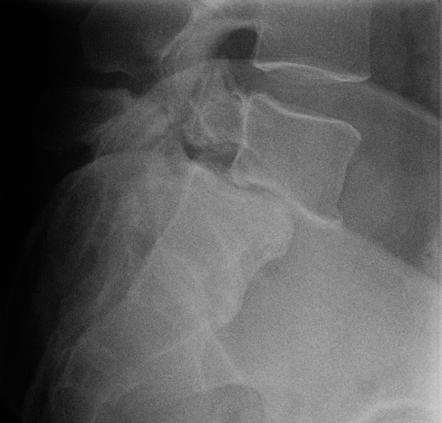

Les troubles statiques de la colonne vertébrale chez l'enfant sont principalement représentés par des scolioses, des cyphoses ou des anomalies de charnière lombosacrée (spondylolyse et spondylolisthésis). Ils nécessiteront toujours une radiographie d'ensemble du rachis. Leur suivi doit être régulier.